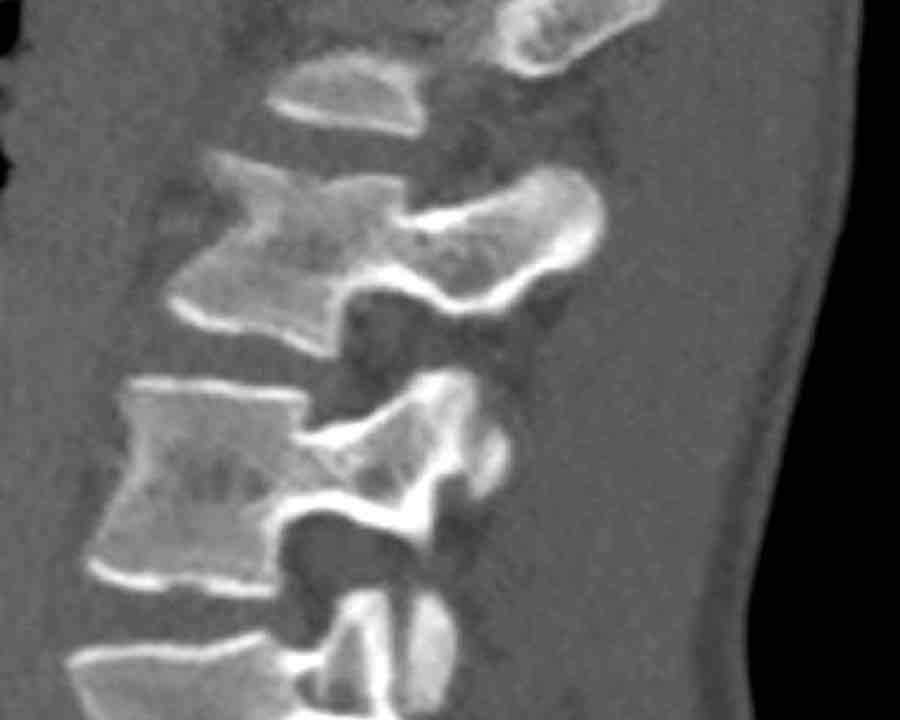

What is the highest AO-type of injury?

Findings

- No C or B injury.

- Fractures of the vertebral body with involvement of both endplates (1+1 points) and posterior wall (2 points).

- In the coronal plane, a sagittal course of the fracture is seen, which is common in burst fractures.

- Bulging of the posterior wall without any other signs of dislocation is the result of the burst fracture.

Therefore no C injury.

Conclusion

Injury type A4